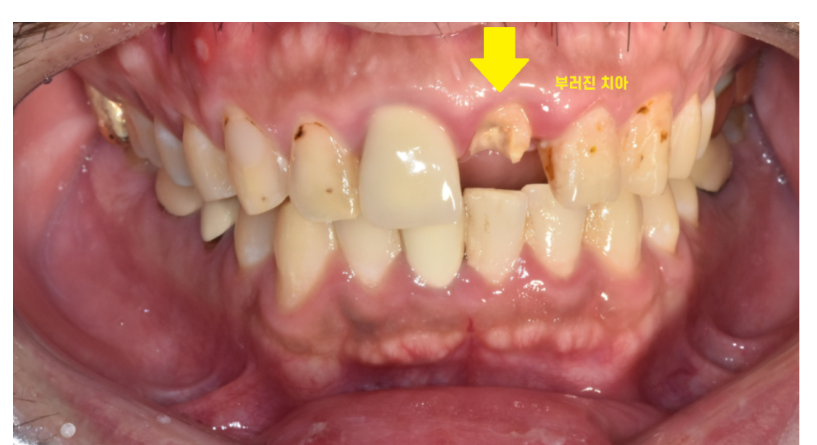

231218 앞니가 부러진 상황

앞니가 갑자기 부러지거나

보철이 탈락했다면..?

보철 제작에 소요될 때까지

마스크를 끼거나 손으로 입을 가리면서 생활해야했습니다.

(앞니 임플란트 환자분들이 이 점때문에 많이 힘들어하세요...)